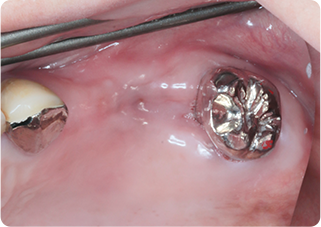

セラミックアンレー症例①

術前

むし歯除去

ラバーダム防湿

術後

| 主訴 | むし歯の治療をしたい |

| 治療期間/回数 | 2週間、2回 |

| 価格(税込) | 77,000円(税込) |

| リスク・副作用 | セラミックの破損、一時的な知覚過敏が生じる場合がある |

| ポイント | ラバーダム防湿をし、唾液や呼気の侵入を防ぎ湿度を下げることで、セラミックの接着力の向上を計った。接着力の向上により、脱離や破折の予防になる。 |